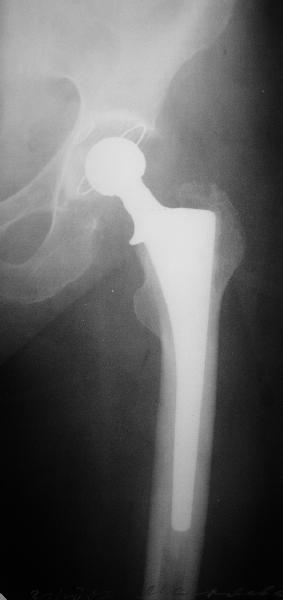

На прошлой неделе пациентке 74 лет, было выполнено цементное эндопротезирование тазобедренного сустава по поводу перелома шейки бедра.Активизирована на следующий день, ходила с костылями, нагрузка полная.Дело близилось к выписке, когда она, подскользнувшись упала в палате и получила то, что  видите на снимках.Что бы Вы стали делать в подобной ситуации? Заранее спасибо.